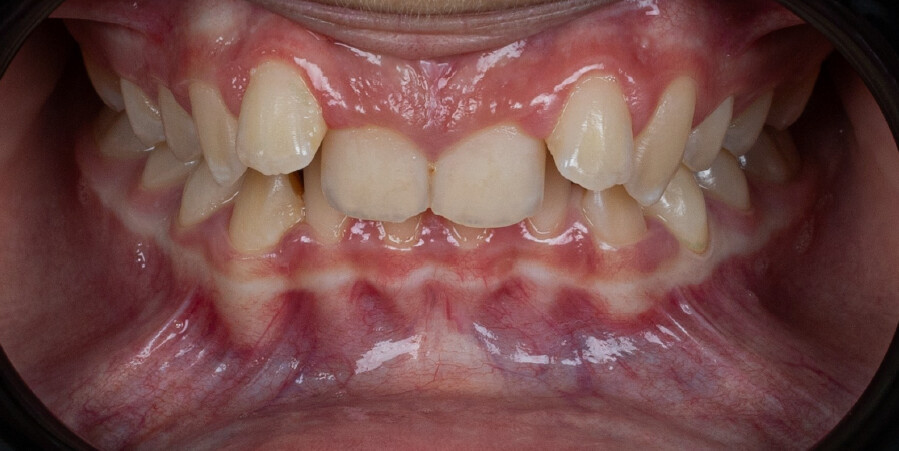

A 13-year-old male patient presented with a deep bite, characterized by near-complete coverage of the mandibular incisors. Clinical evaluation revealed bi-arch crowding, dental rotations, and proclination of the maxillary lateral incisors, contributing to the patient’s esthetic concerns. The facial profile was retrusive, consistent with mandibular retrognathism, and no significant periodontal abnormalities were detected.

The patient presented with a skeletal Class II relationship with bilateral molar and canine Class II and a Class II division 2 dental pattern. The deep bite was associated with anteroinferior crowding and an accentuated Curve of Spee. Facial analysis revealed good symmetry, a slightly increased lower facial third, and a convex profile characterized by mandibular and chin retrusion. Lip competence was mildly reduced, with a decreased nasolabial angle and mentalis hyperactivity, all of which compromised overall facial harmony.

Chief complaint: The patient’s primary concerns were the gummy smile associated with a deep bite, and the limited space available for anterior alignment. He also expressed dissatisfaction with the position of the maxillary lateral incisors, describing them as being positioned “too high.”